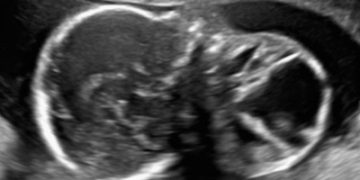

Casi del Mese di Marzo 2023

Cari soci, finalmente online le soluzioni dei casi per il mese di Marzo!!! Grazie a Ilaria Fantasia e Gabriele Saccone!! Caso 1 [pdf-embedder url="https://www.sieog.it/wp-content/uploads/2023/03/caso-clinico-Fantasia-risposta-marzo-2023.pdf" title="caso...